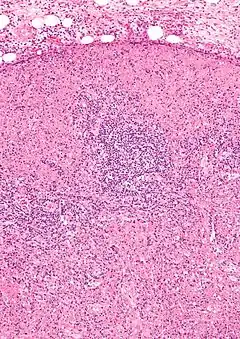

Microfotografia de un nódulo linfático de un paciente afectado por la enfermedad de Kikuchi-Fujimoto. Existen áreas de necrosis y abundantes histiocitos.

Para realizar el diagnóstico, la prueba clave es la biopsia de uno de los ganglios afectados, que muestra hallazgos microscópicos característicos, principalmente áreas de necrosis que distorsionan la estructura del ganglio y la presencia de numerosos histiocitos en las zonas limítrofes de las áreas con necrosis, con escasa presencia de polimorfonucleares neutrófilos y células plasmáticas. Con base en estos hallazgos la enfermedad ha sido denominada linfadenitis histiocítica necrosante.